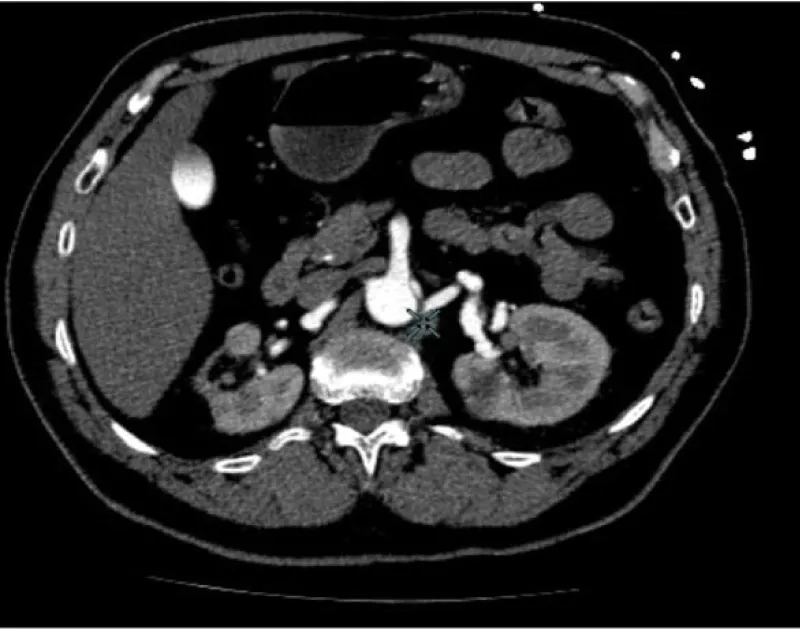

FMD is a rare disease that is often diagnosed solely based on clinical and angiographic findings. In our case, CT angiography mages show the typical appearance of a “pearl necklace” characteristic of FMD (Figure 3). Although the three arterial layers may be affected, the most frequent and responsible of the classical radiological image is the medial dysplasia, alternating areas of thickening and fibrosis in the middle and aneurysmal dilatations with loss of the internal elastic lamina.

Figure 3: CT angiography mages show the typical appearance of the “pearl necklace” characteristic of FMD.